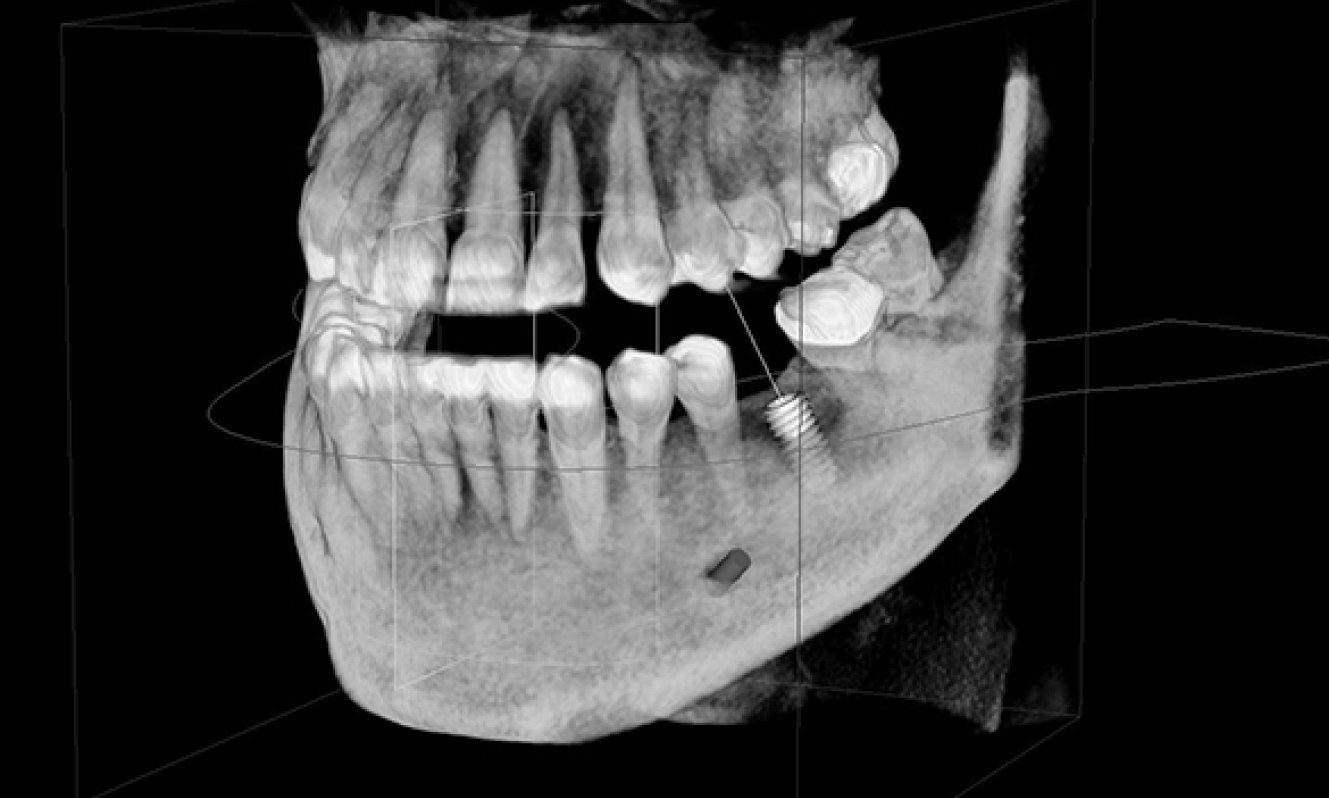

CBCT 3D Imaging

A 3D CBCT scan is a specialized dental imaging technique that provides detailed three-dimensional views of the teeth and jawbone. It's particularly useful for precise implant planning, endodontic evaluations, orthodontic treatment, and assessing temporomandibular joint (TMJ) conditions. CBCT scans offer comprehensive insights for accurate diagnosis and treatment planning in dentistry.